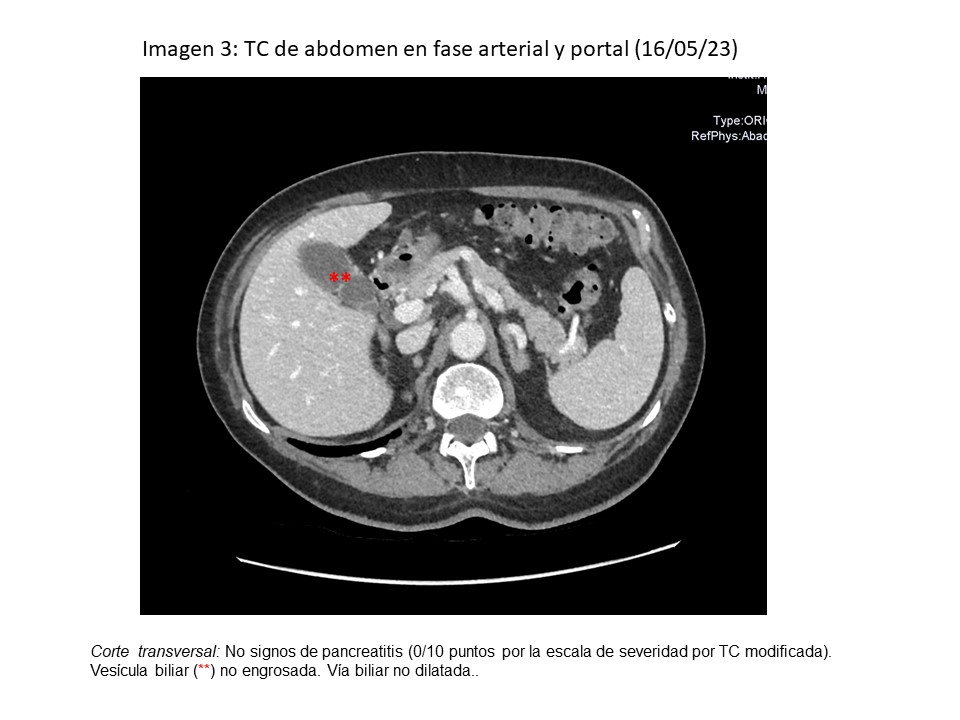

• Ecografía clínica-AP (31/05): páncreas poco visible, hiperecoico, no delimitado; porta de 9 mm con vía biliar ligeramente dilatada (3,9 mm), vesícula con barro biliar, paredes finas.

• TC abdomen en fase arterial-portal (16/05): normal.